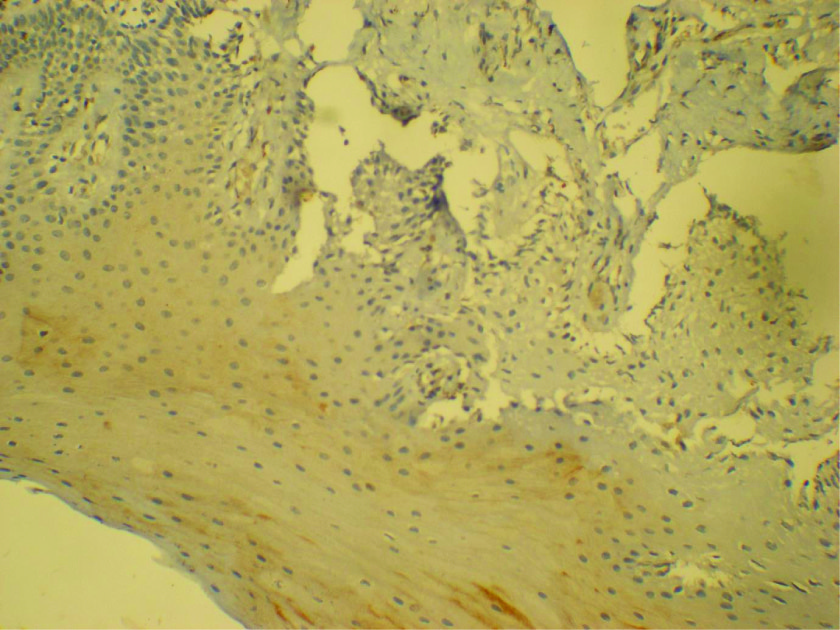

Ck-19 staining in the basal cells of NRM - 40x

Diffuse positivity of NSE in NRM

Faint positivity to synaptophysin in NRM 20X

Faint CD99 staining in the basal cells of NRM - 20X

Based on the criteria followed for assessing the expression in the normal mucosa, it was seen that a positive staining was obtained in all the 10 cases for NSE [Table/Fig-8], in eight cases for Synaptophysin [Table/Fig-9] and in six cases for CD99 [Table/Fig-10]. The staining was stronger,diffuse and extended to the superficial layers in case of NSE, and was specifically restricted to the basal layers in case of CD99 [Table/Fig-10].